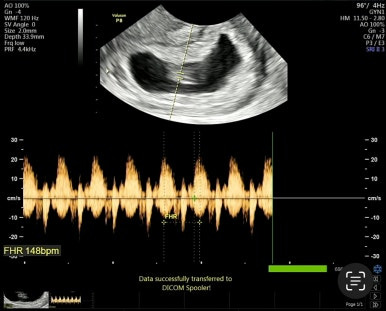

7주 1일차

처음으로 아기를 볼 수 있고, 심장소리를 처음 들을 수 있다!

아기가 1cm 정도 밖에 안되는데 심장소리가 우렁찬게 너무 신비스럽다 :)